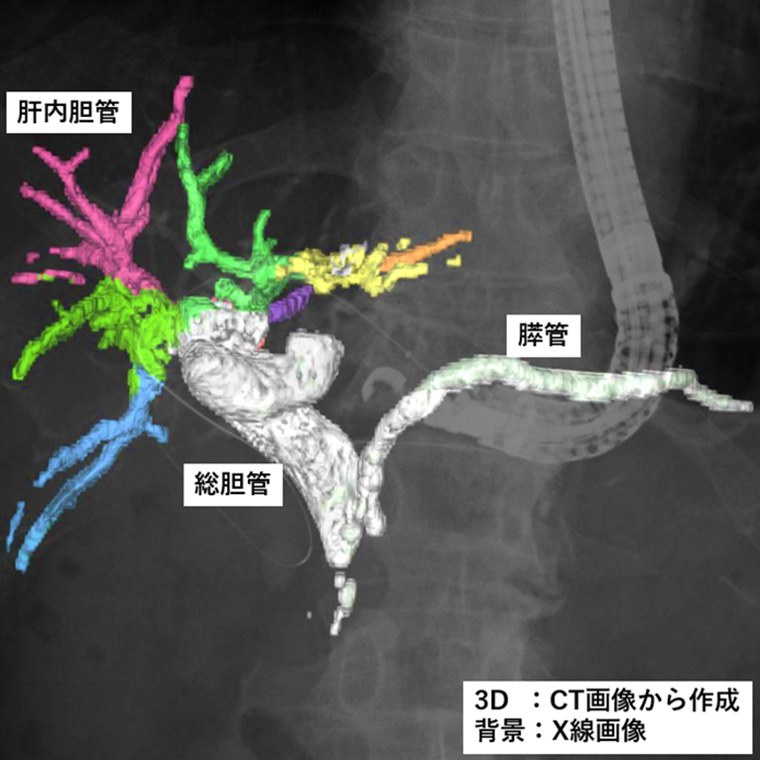

また、今回発売する二つのモデルは、2025年4月に発売したソフトウェア「VisualAID-ERCPプランニング-」*7にも対応。本ソフトウェアは、ERCP中にCUREVISTAシリーズで撮影したX線透視画像上に3Dで作成した胆管・膵管の画像を重ねて表示することで、臓器との重なりなど解剖学的構造の把握が容易になることが期待できます。本ソフトウェアでは、これまでCT画像とMRCP画像*8で3D画像を作成する必要がありましたが、今回新たにCT画像のみで3D画像を作成できるようになりました。これにより、MRI撮影を実施しない医療機関での対象被検者の増加が見込まれます。さらに3D画像作成時にCT画像とMRCP画像の位置合わせの作業が不要となることでワークフローの向上が期待できます。当社のIT技術とX線透視装置を連携させた新しいワークフローにより、医師の診療の高度化・効率化に貢献します。

ERCP中に撮影したX線透視画像上にCT画像を用いて作成した胆管・膵管3D像を重畳表示している様子